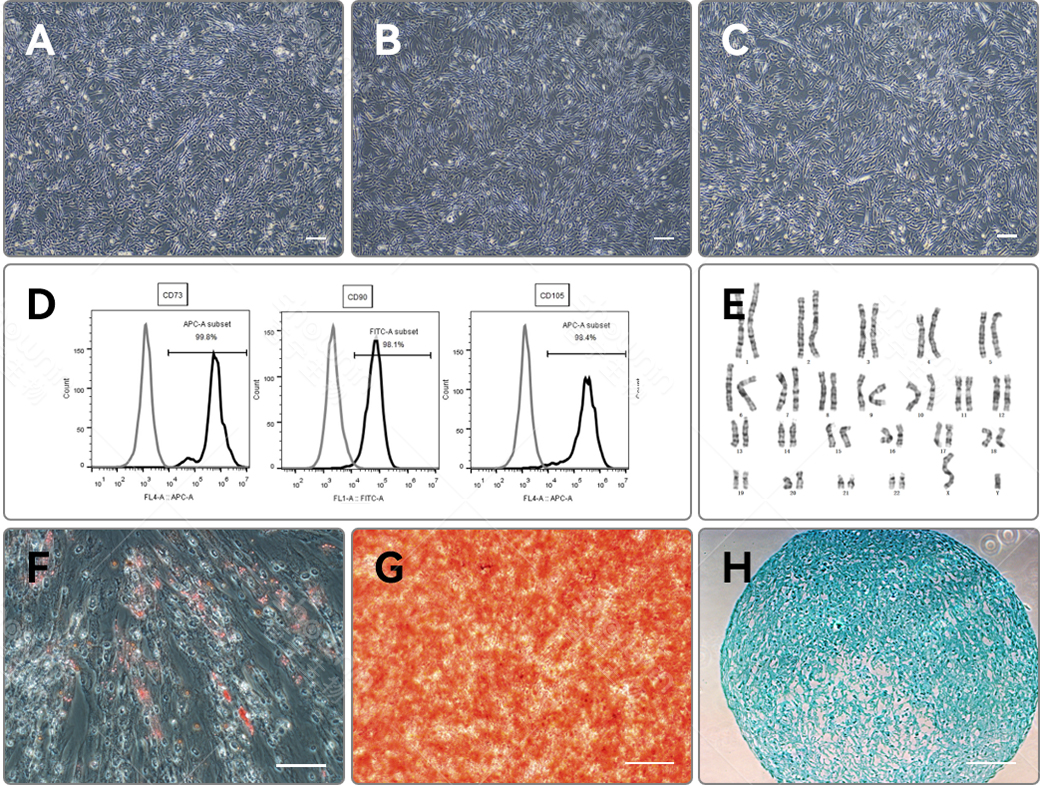

細胞形態および同定

A、B、C:連続継代培養された初代 hMSC細胞のP3、P4、P5代3日目の形態図示。接種密度6000/cm²、培地使用量0.2 mL/cm²、T25フラスコで3日間連続培養。

D:連続培養された初代hMSC細胞(P5)の表面マーカー検査(CD73+ / CD90+ / CD105+)。E:連続培養された初代hMSC細胞(P5)の染色体核型検査。

F、G、H:連続培養された初代hPSC細胞(P5)の硬骨・脂肪・軟骨形成の3系列への分化能実験。F:脂肪への分化(オイルレッド染色法)。 G:硬骨への分化(アリザリンレッド染色法)。 H:軟骨への分化(アルシアンブルー染色法)スケール:200μm。